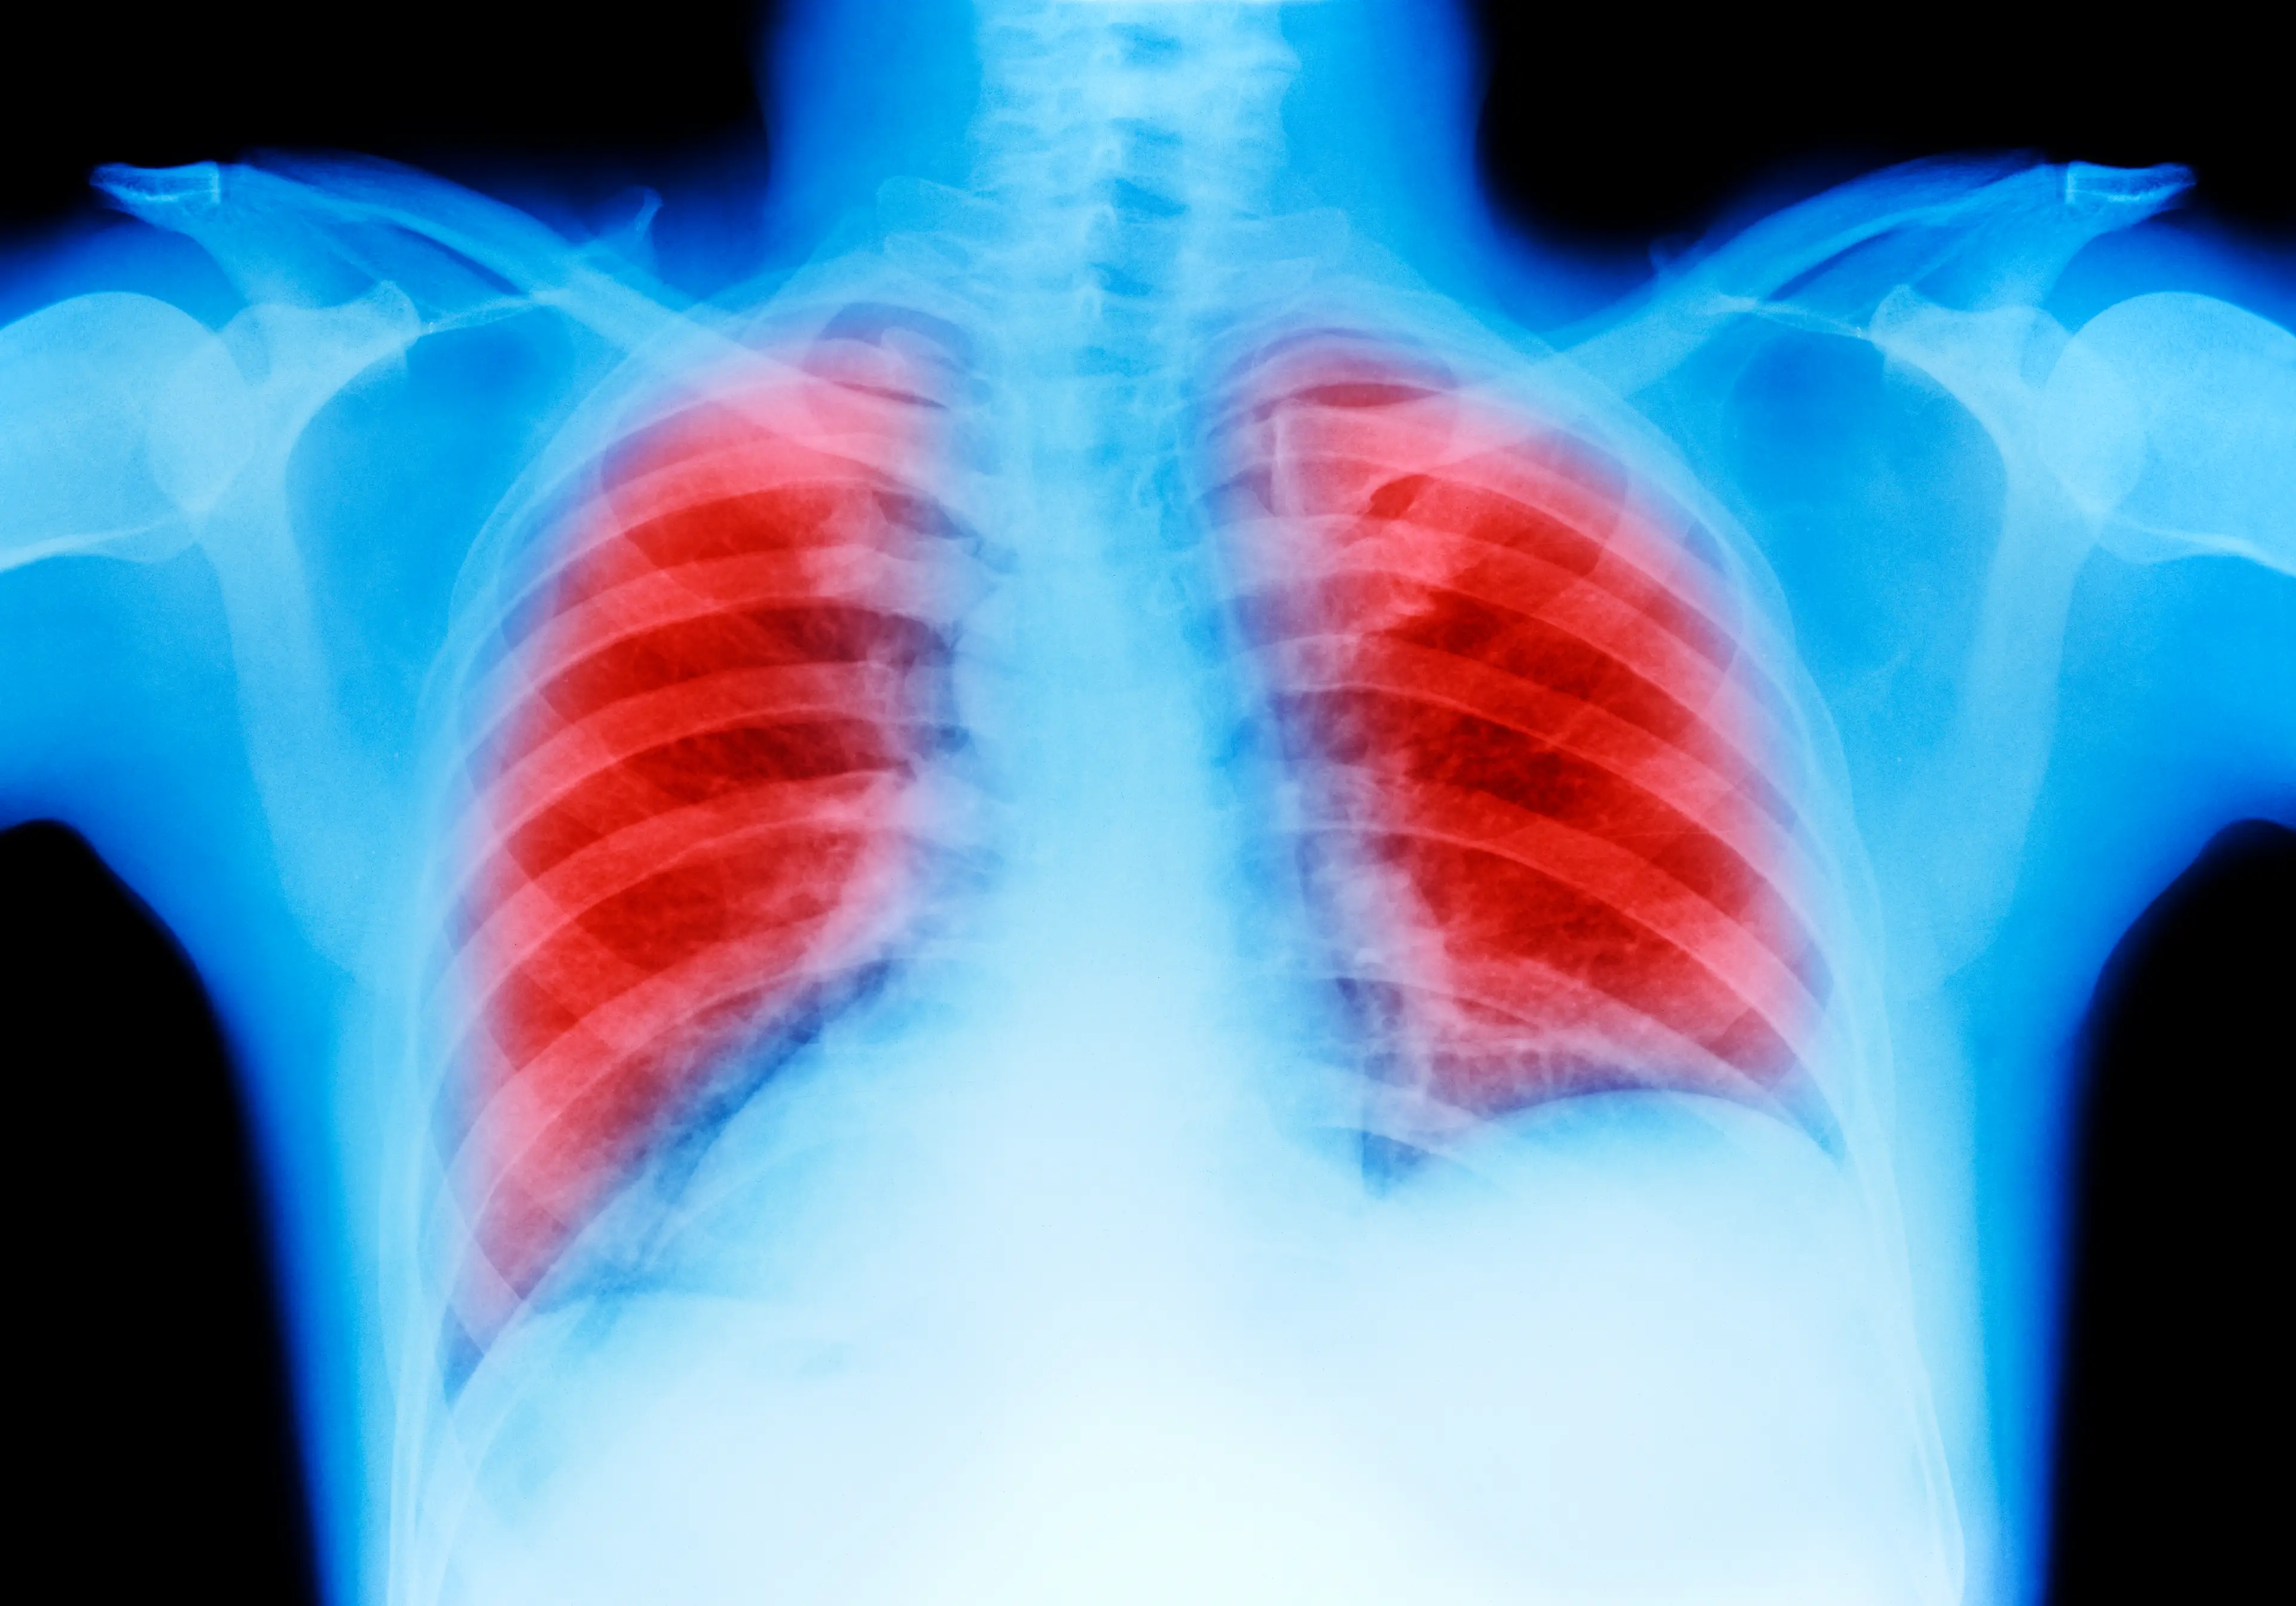

According to the NHS, silicosis is typically a long-term disease which develops after a person inhales crystalline silica dust over an extended period of time.

Symptoms of silicosis can include shortness of breath, a persistent cough and tiredness.

As the condition progresses, a patient will struggle to do day-to-day activities without feeling out of breath. They may also become more susceptible to other life-threatening conditions such as pulmonary hypertension, chronic obstructive pulmonary disease and even lung cancer.

Some patients can also develop acute silicosis, which occurs when someone inhales high amounts of the dust over a short period of time.